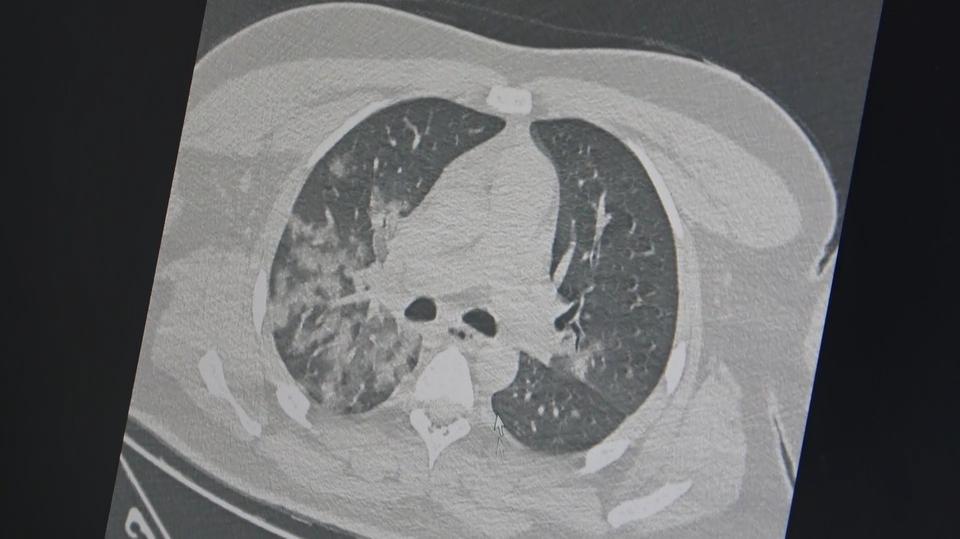

Göğüs Hastalıkları Uzmanı Prof. Dr. Şevket Özkaya, "Özellikle gençlerin kovid-19 sonrası bozulmuş damar yapısı, ağır egzersiz ve spor ile ölümcül kalp krizlerine neden oluyor. Ani artan genç ölümlerinden Kovid-19 aşıları değil, korona virüsünün ... haberin devamı için tıklayın